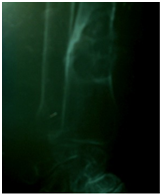

A 64-year-old man, without significant medical history, presented with multiple bone pain.These pains were not calmed by analgesics. The general condition was maintained and physical examination was normal. There were no clinical signs of Hypercalcemia (polyuria, gastrointestinal symptoms). Biology showed calcium at upper limit level: 2.66mmol/l (the reference range for the laboratory was 2.2-2.6mmol/l). We did X-rays analyses and a CT-scan that showed multiple lytic lesions especially on peripheral bones (Figure 1). Secondary bone metastases were suspected therefore bone scintigraphy was indicated. He did a Tc-99m MDP whole body bone scan which showed multiple areas of intense uptake, within both axial and peripheral skeleton, on the same sites of lytic lesions found on X-rays analyses and CT-scan (Figure 2). That aspect recalls the aspect of disseminated brown tumors, so we dosed the PTH in serum, which was very high: 2003µg/l (the reference range for the laboratory was11-62µg/l).

Figure 2 Bone scan showing multiple areas of intense uptake.